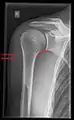

X-ray

Projectional radiography views of the shoulder include:

- AP-projection 40° posterior oblique after Grashey

The body has to be rotated about 30 to 45 degrees towards the shoulder to be imaged, and the standing or sitting patient lets the arm hang. This method reveals the joint gap and the vertical alignment towards the socket.[24]

- Transaxillary projection

The arm should be abducted 80 to 100 degrees. This method reveals:[24]

- The horizontal alignment of the humerus head in respect to the socket and the lateral clavicle in respect to the acromion

- Lesions of the anterior and posterior socket border, or of the tuberculum minus

- The eventual non-closure of the acromial apophysis

- The coraco-humeral interval

- Y-projection

The lateral contour of the shoulder should be positioned in front of the film in a way that the longitudinal axis of the scapula continues parallel to the path of the rays. This method reveals:[24]

- The horizontal centralization of the humerus head and socket

- The osseous margins of the coraco-acromial arch and hence the supraspinatus outlet canal

- The shape of the acromion

This projection has a low tolerance for errors and, accordingly, needs proper execution.[24] The Y-projection can be traced back to Wijnblath’s 1933 published cavitas-en-face projection.[25]

CR. shoulay film.